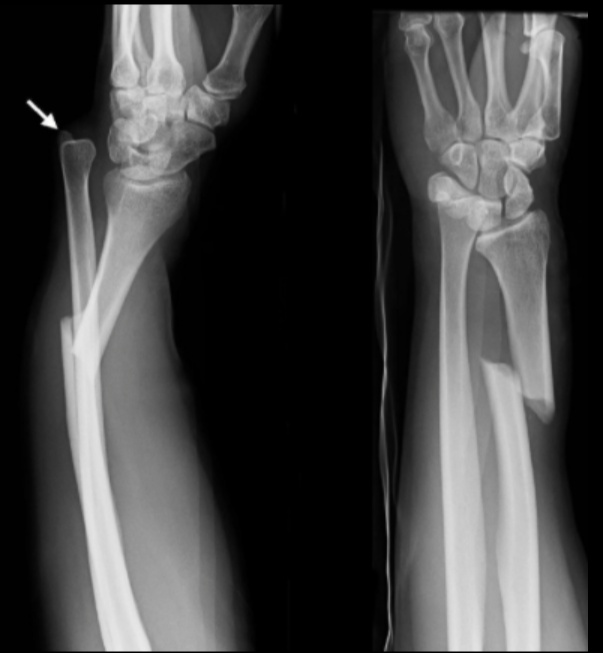

Galeazzi

Forearm injury involving fracture of the distal third of the radial shaft with concurrent disruption of the distal radioulnar ligament.

.,

Galeazzi fractures usually occur due to direct trauma or a fall onto an outstretched, pronated forearm.

A Galeazzi fracture presents with pain, swelling, and visual deformity of the distal forearm.

Because of the instability of a Galeazzi fracture, they are treated surgically to reduce the radius and with casting to keep the distal radioulnar joint reduced.

As with Monteggia fractures, the traumatic nature of this fracture puts patients at risk of compartment syndrome.